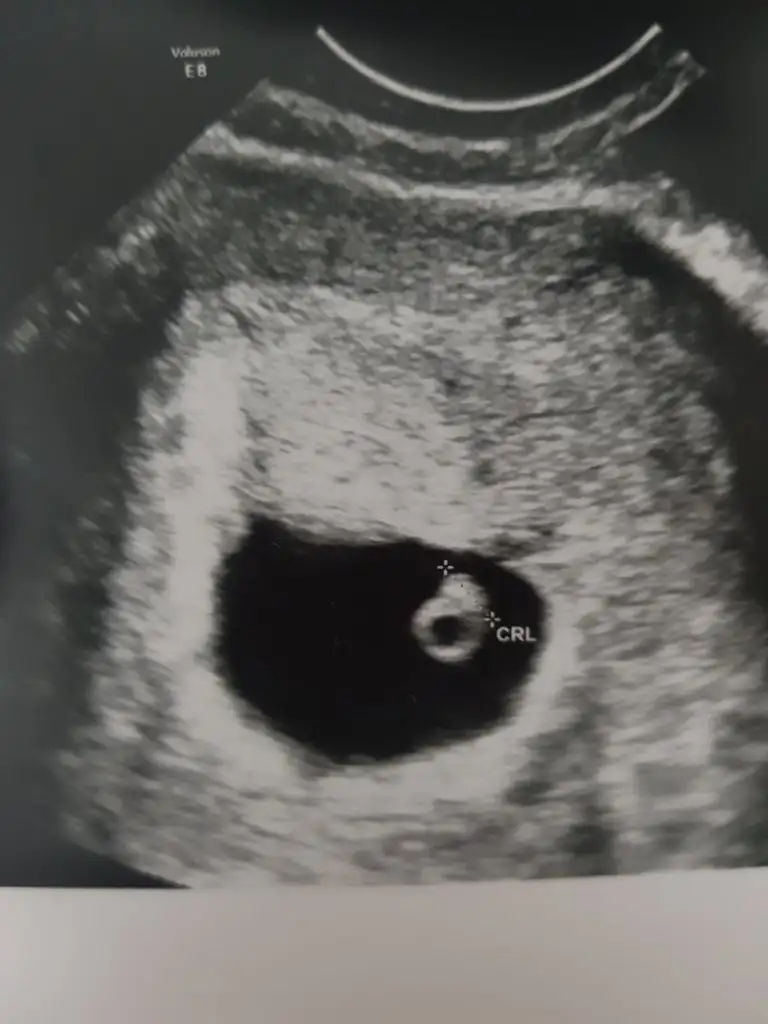

Ramzi teorisine göre cinsiyet tahmini yapacagim ilk ultrasyon resminizi atin bakiyim. Eger cinsiyetiniz belliyse hic söylemeeyin bakalm dogru tahmin edebilecekmiyim daha dogrusu ramzi teorisi hakli cikacak mi?

Senin bebeğin kiz miBenimkine de bakar mısınız ? Alttan ultrason

Cin5+5 vajinal ultrason Eki Görüntüle 3026039

Cinsiyet kiz mi acaba5+5 vajinal ultrason Eki Görüntüle 3026039

Emin olmamakla birlikte kiz .şu anda kaç haftaliksinizEki Görüntüle 3066106 6+0 karından

Ay inşallah bir oğlum var birde kızım olursa bal kaymakEmin olmamakla birlikte kiz .şu anda kaç haftaliksiniz

Ay inşallah bir oğlum var birde kızım olursa bal kaymaktabiki hayırlısı olsun şaka bı yana evlat evlattir bu dünkü usg 6+1 im yani :)